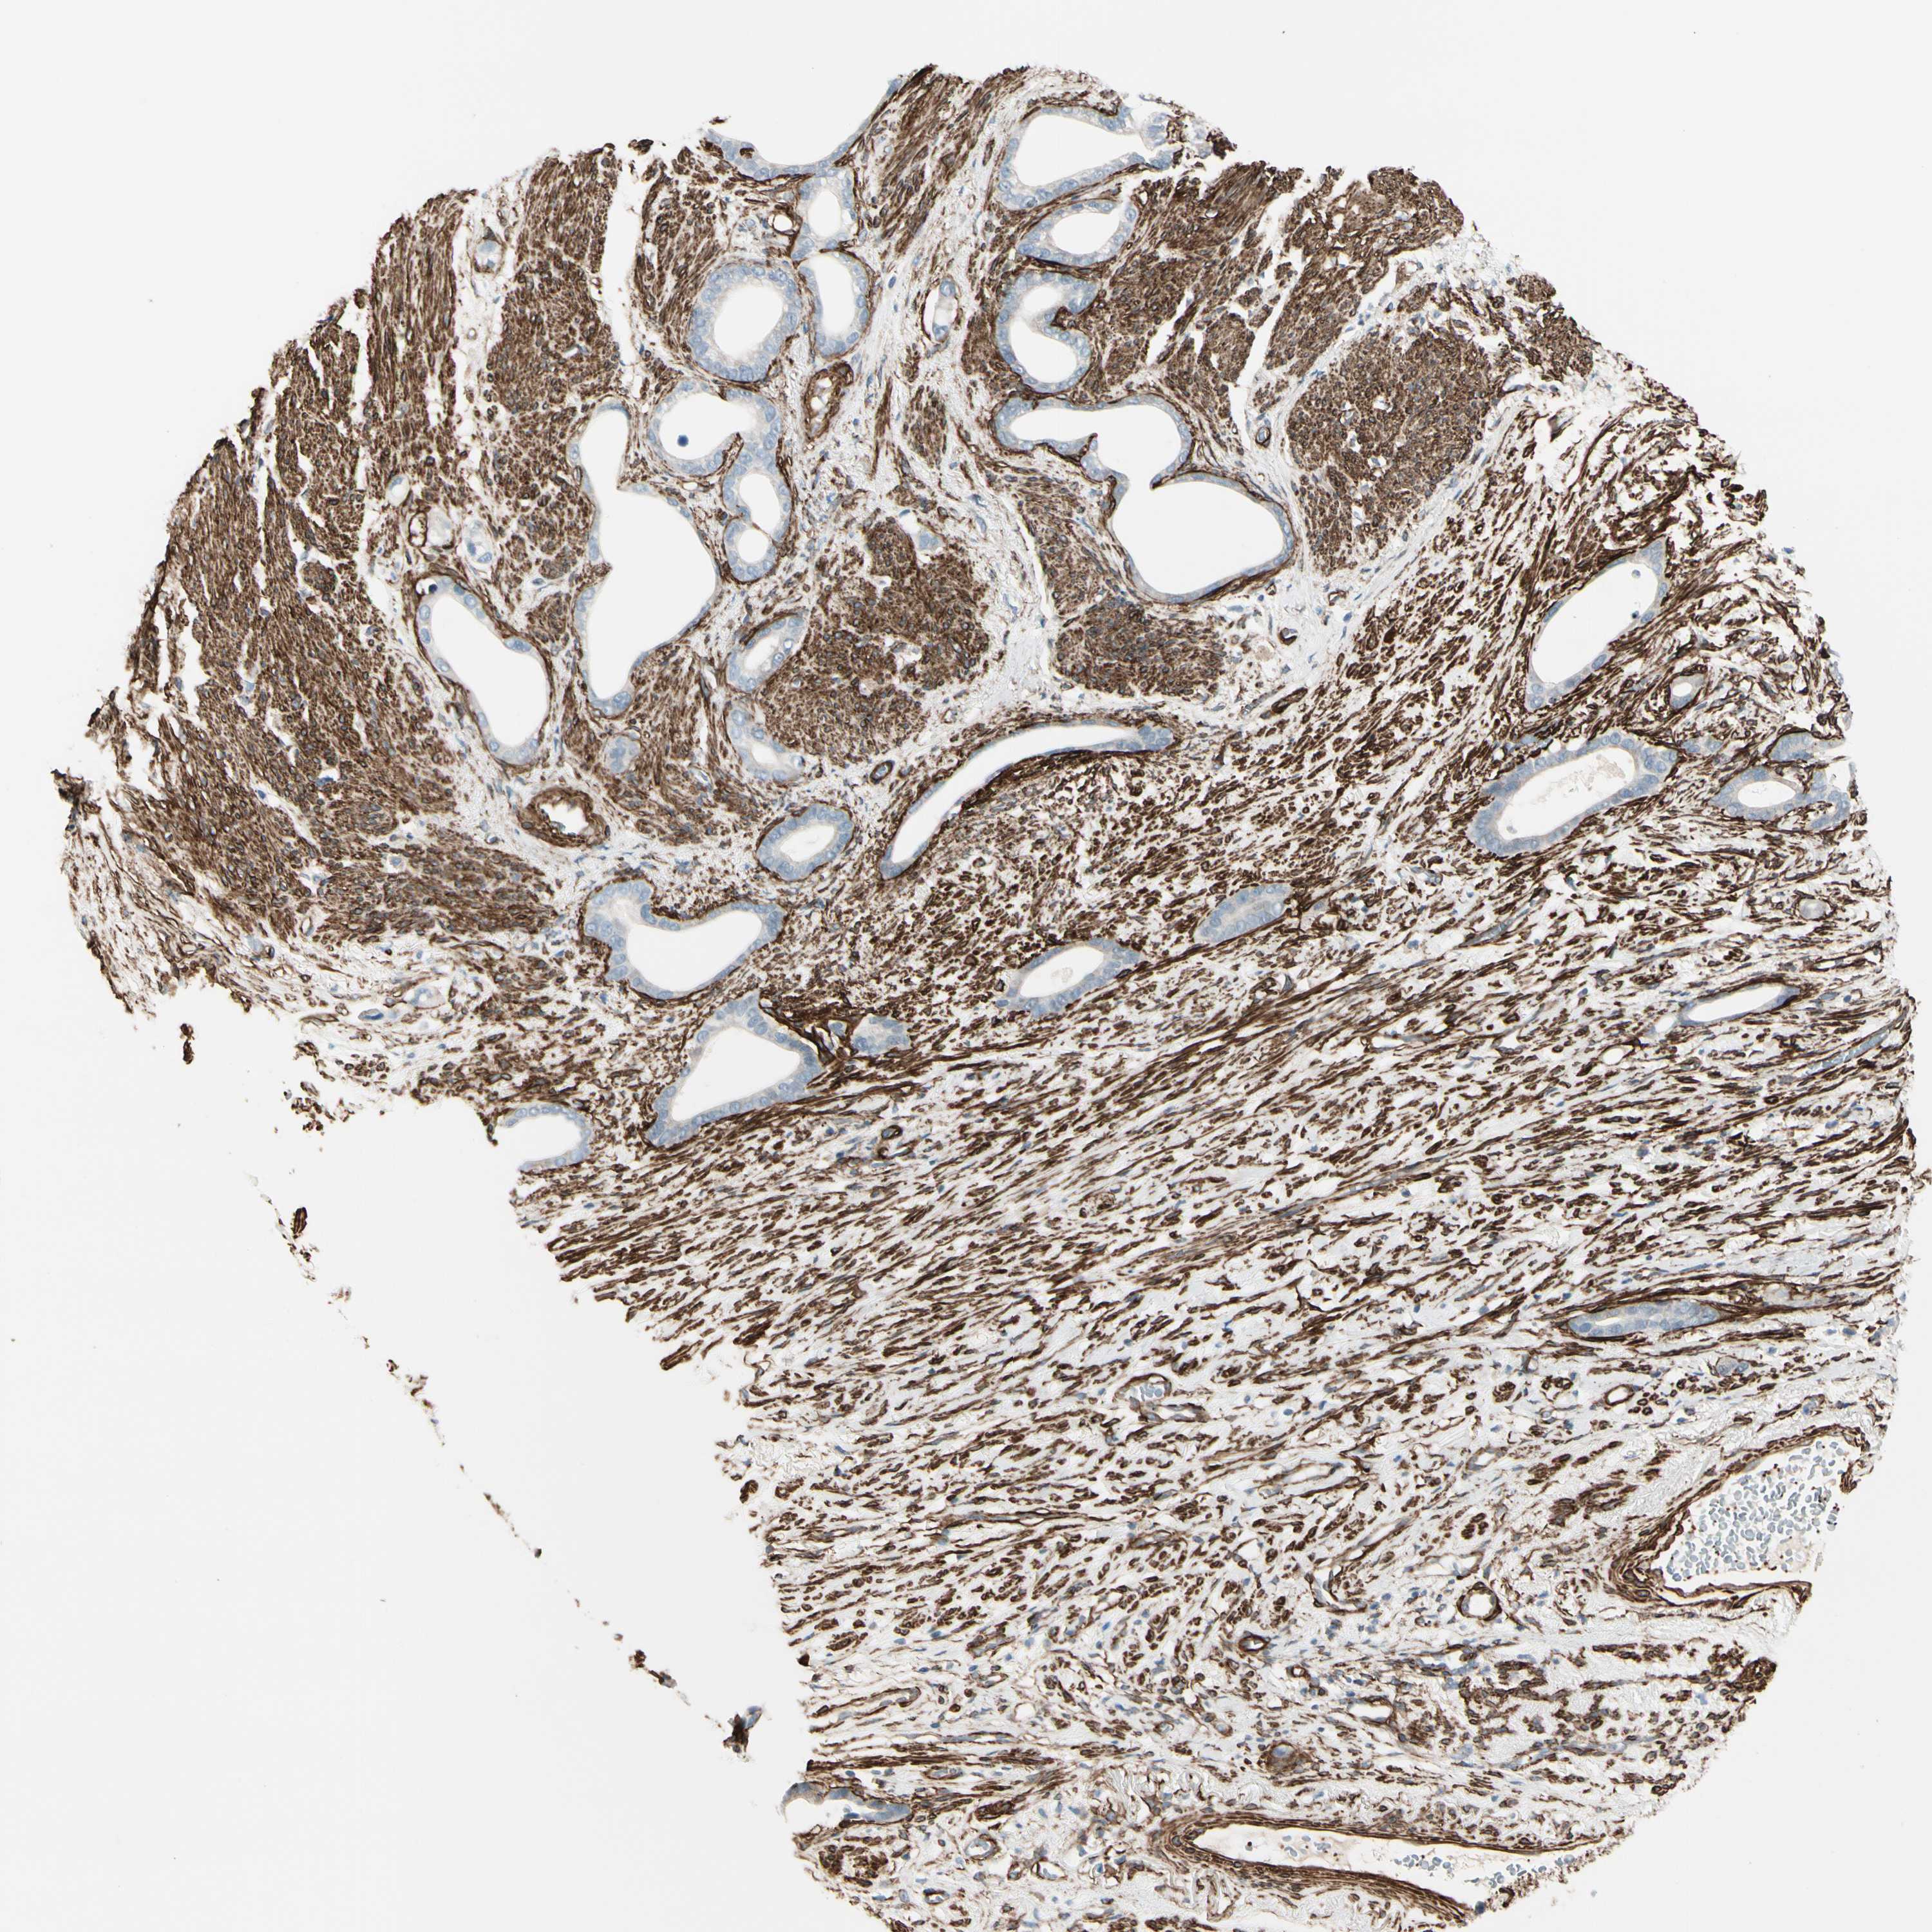

STOMACH CANCER - Protein expressioni

A mouse-over function shows sample information and annotation data. Click on an image to view it in a full screen mode. Samples can be filtered based on level of antibody staining by selecting one or several of the following categories: high, medium, low and not detected. The assay and annotation is described here.

Note that samples used for immunohistochemistry by the Human Protein Atlas do not correspond to samples in the TCGA dataset.

Antibody stainingi

Antibody staining in the annotated cell types in the current human tissue is reported as not detected, low, medium, or high, based on conventional immunohistochemistry profiling in selected tissues. This score is based on the combination of the staining intensity and fraction of stained cells.

Each image is clickable and will lead to virtual microscopy that enables deeper exploration of all samples and also displays staining intensity scores, fraction scores and subcellular localization as well as patient and tissue information for each sample.

Antibody HPA008066

Antibody HPA017330

Antibody CAB000006

Staining

High

Medium

Low

Not detected

Intensity

Strong

Moderate

Weak

Negative

Quantity

>75%

75%-25%

<25%

None

Location

Nuclear

Cytoplasmic/membranous

Cytoplasmic/membranous,nuclear

Adenocarcinoma, NOS